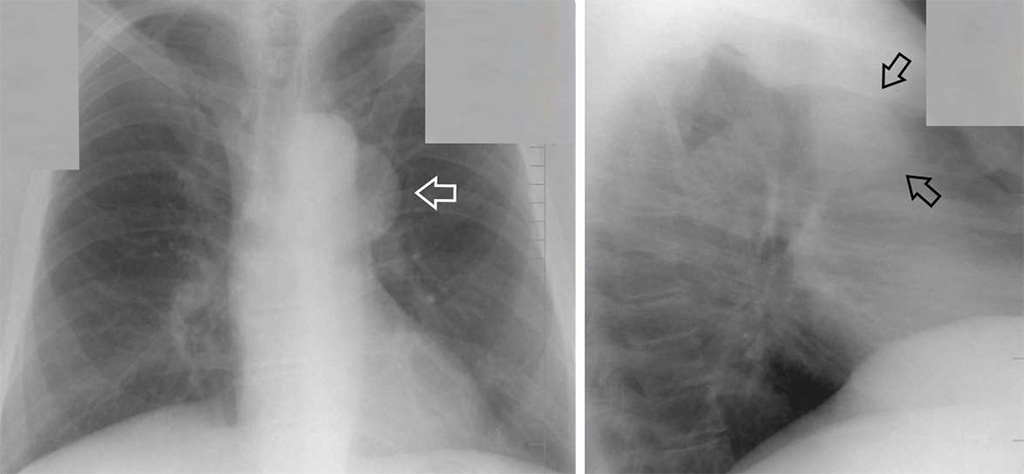

Рентгеновские снимки опухоли Панкоста